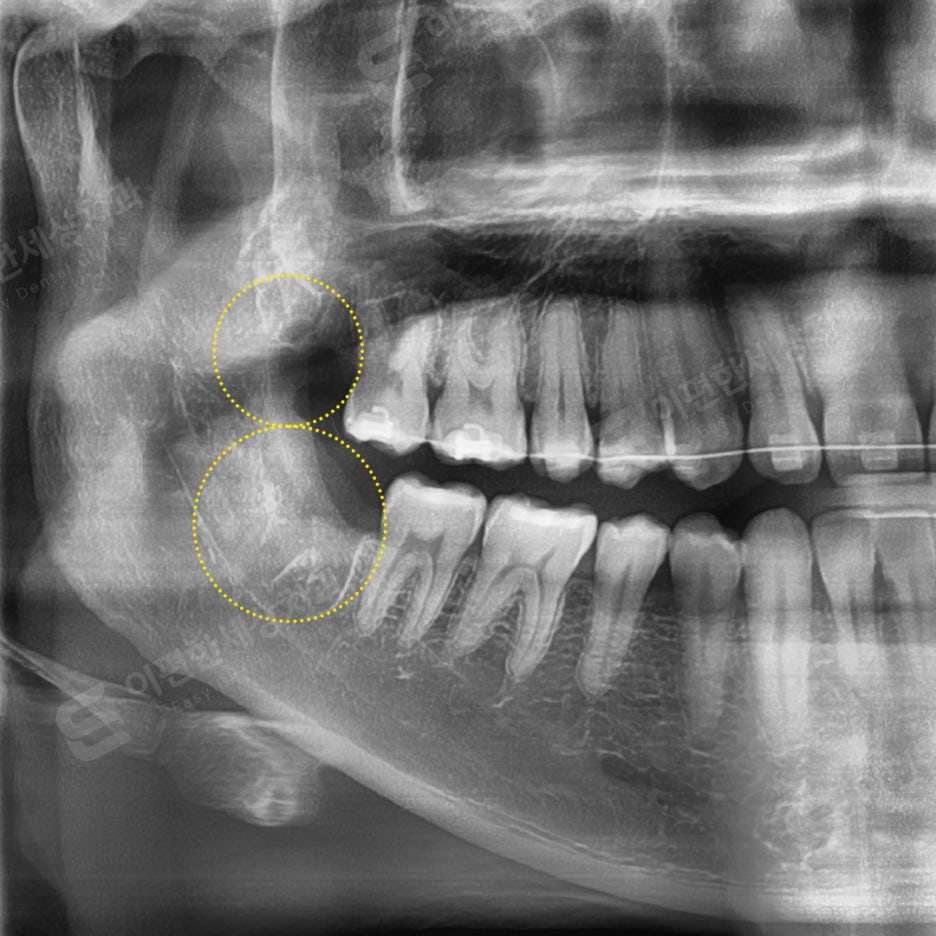

촬영 일자 24.02.16

인터넷 검색 후 내원, 당일 발치 케이스

#48 완전매복 발치

치근단 신경이 닿아서

CT 촬영 후 발치

#18 일반 발치